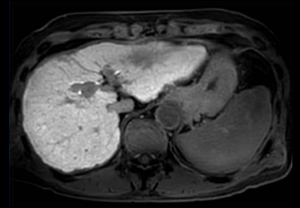

Cine 2D BFFE (4 CAV)

Elition X 3.0T

東京警察病院